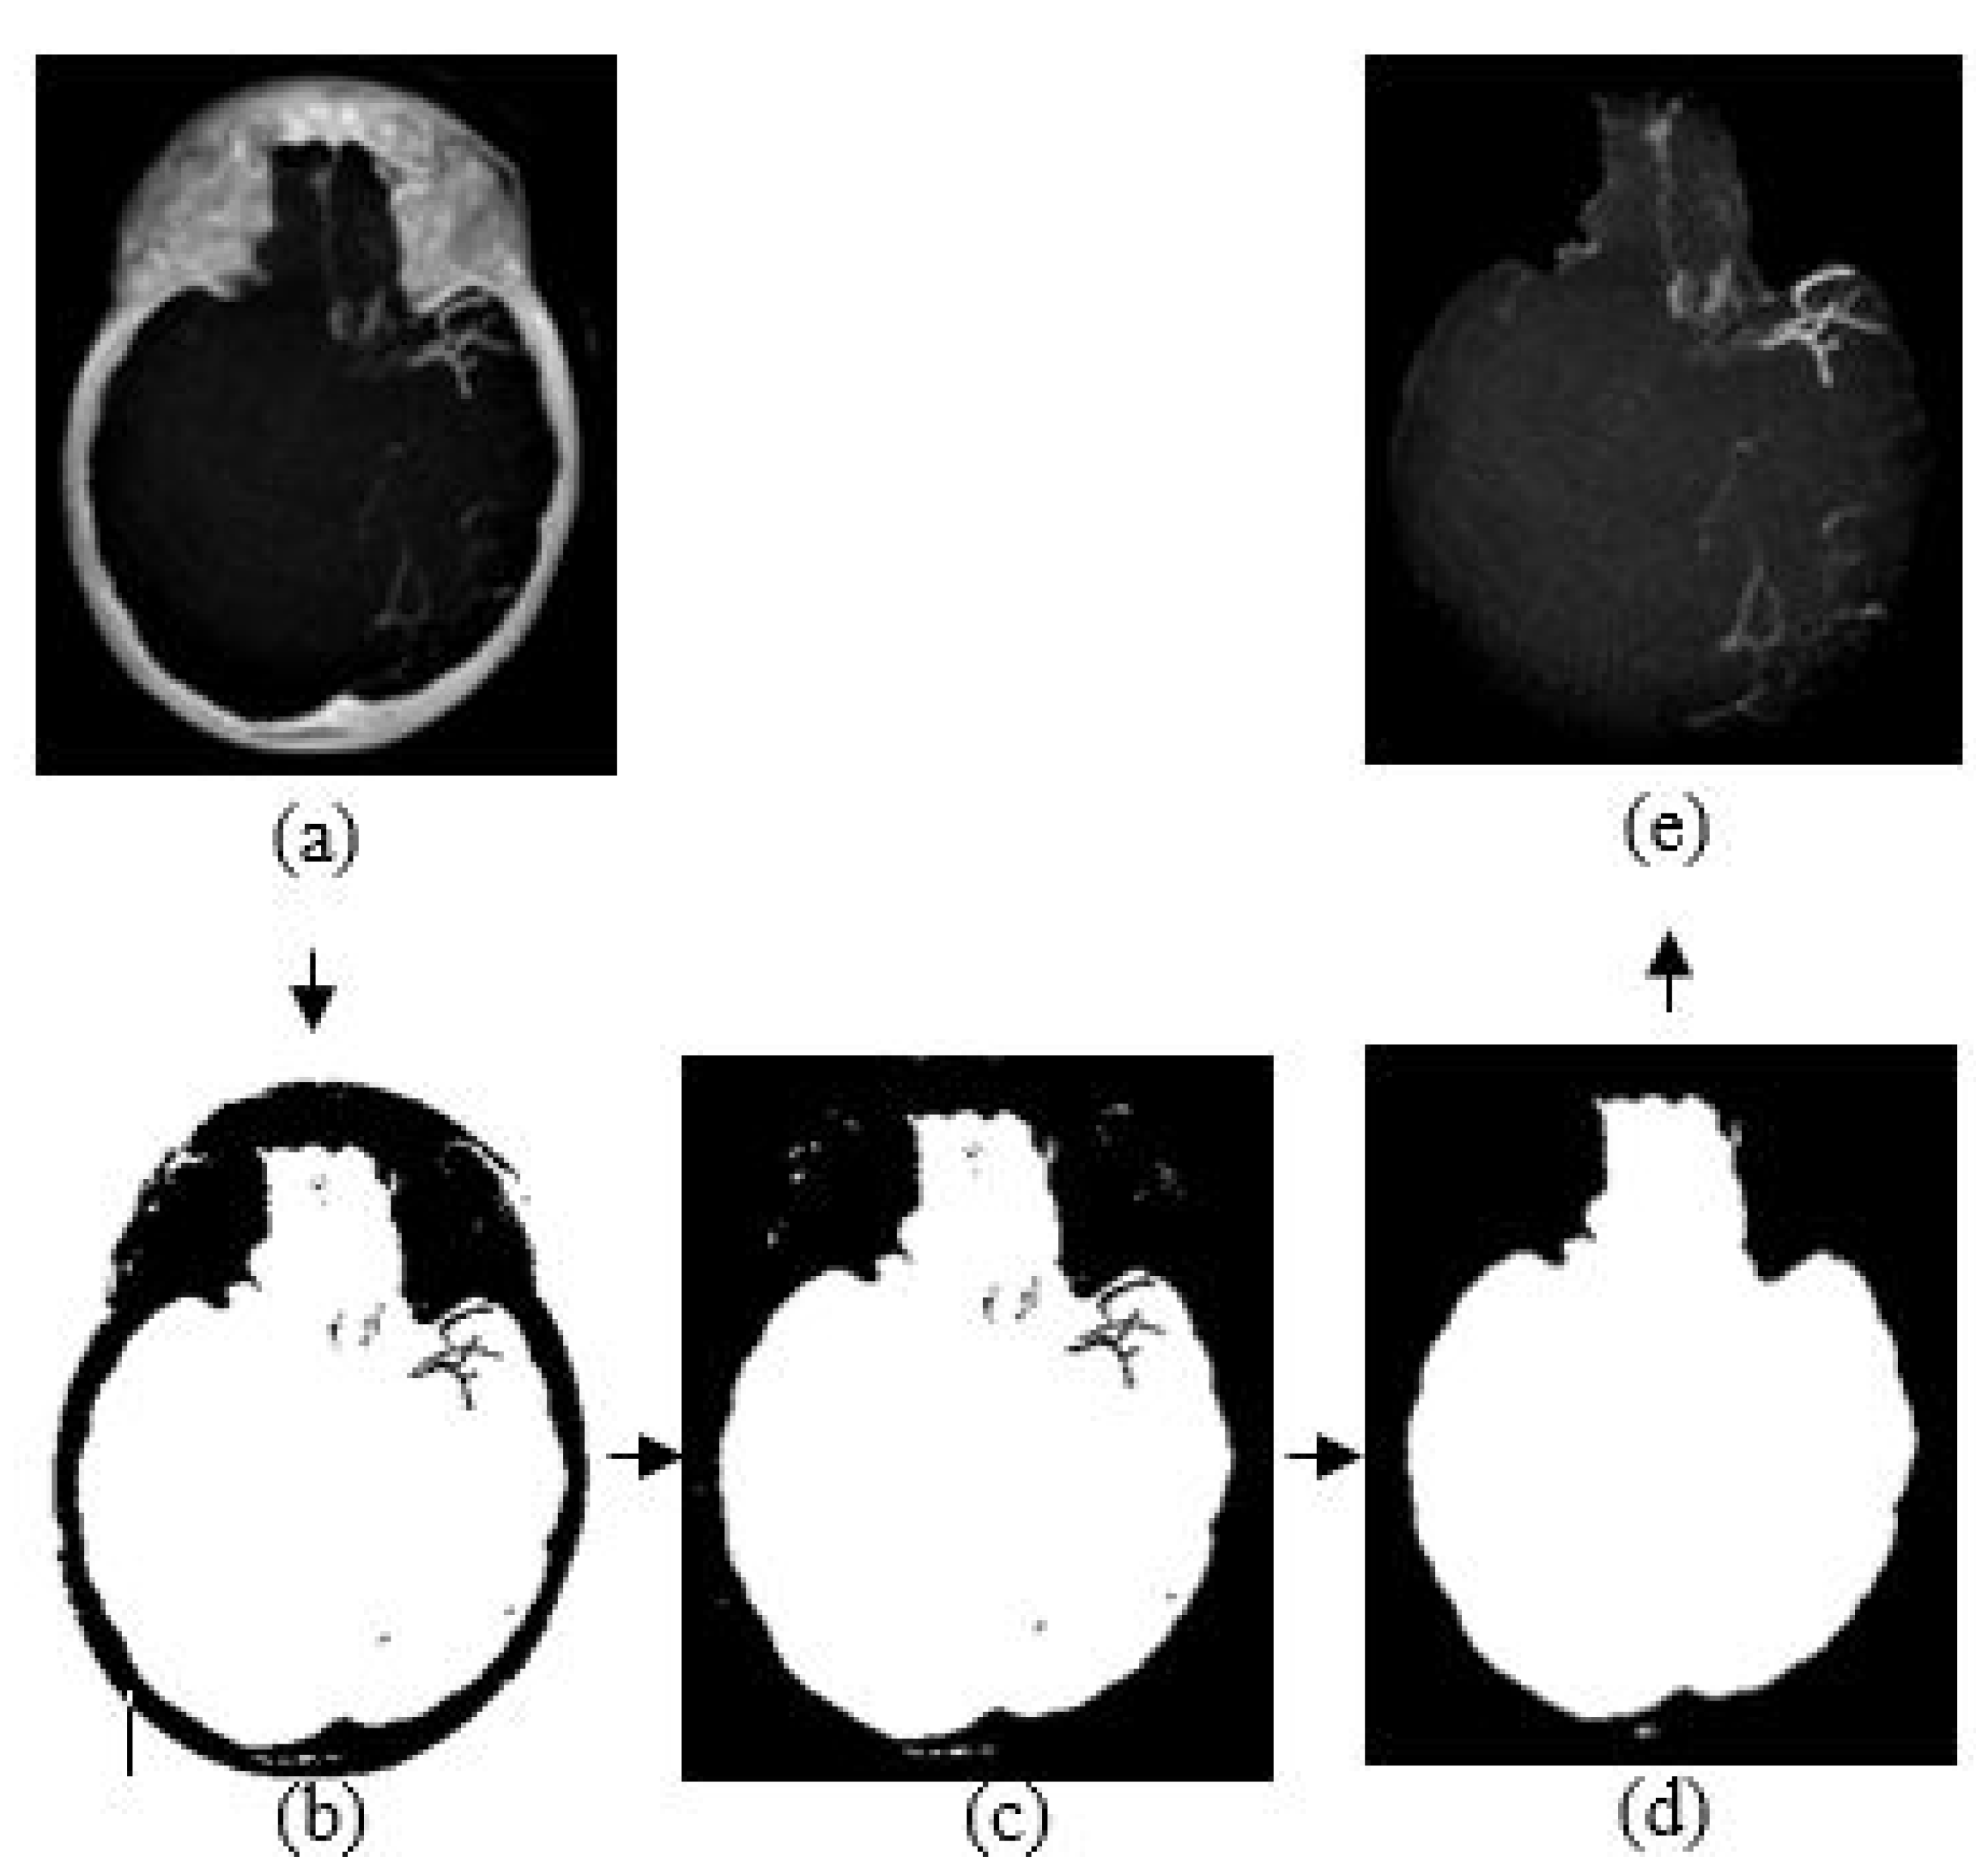

The purpose of skull removal is to obtain an MIP image without the skull to facilitate collateral vessel enhancement and segmentation. A mask image of the region of interest (brain area without the skull) is obtained for the skull removal to avoid any false-positive results since the intensity range of the skull is quite close to the intensity range of blood vessels. Skull removal algorithm based on morphological reconstruction, which relies on the connected components and region properties, is used. Skull will be removed based on the labeling connected components and computation of region properties. Figure 4 shows the resultant images obtained throughout the skull removal process to obtain blood vessel structures from an MIP image.

Figure 4.

The algorithm of skull removal. (a) MIP input image, (b) binary image, (c) removing object touching the binary image boundary, (d) mask image, and (e) region of interest, masked out from mask image.

The skull removal involves several processes. MIP image obtained from Section 3.3 is used as the input image for this purpose. The first process is to convert the input image into a binary image. To achieve this, we use a thresholding method () where x is a scalar value that is obtained from a mean value of input image, I. The result is as illustrated in Figure 4b. The second process is to eliminate unwanted region; in this case, the white region surrounding the outer area of the skull in Figure 4b. This area is also known as the area connected to the image border. Hence, to remove this, we use the method that removes/clear out all connected components or pixels connected to the image boundary which are the outer white pixels surrounding the skull region. The result image obtained is illustrated in Figure 4c.

The third process is to create a mask image with only white pixels in the foreground and black pixels in the background. The process involves a flood-fill operation that will change connected background pixels (0 s) to foreground pixels (1 s) and a measurement of area for each region. Then, by selecting the largest area, what left is the brain region as illustrated in Figure 4d; the mask image. Lastly, the final process is to obtain the MIP input image without the skull. By performing an element-by-element multiplication involving the MIP input image and the mask image, we obtain the final result as illustrated in Figure 4e.